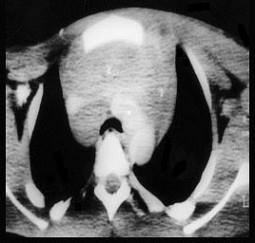

问题 血友病患者突发胸闷,气急,体查见颈静脉显露,嘴唇发干,影像学检查如图,最可能的诊断为 ( )

选项 A、纵隔积液 B、胸腺瘤 C、淋巴瘤 D、结节病 E、纵隔自发性出血

答案 E